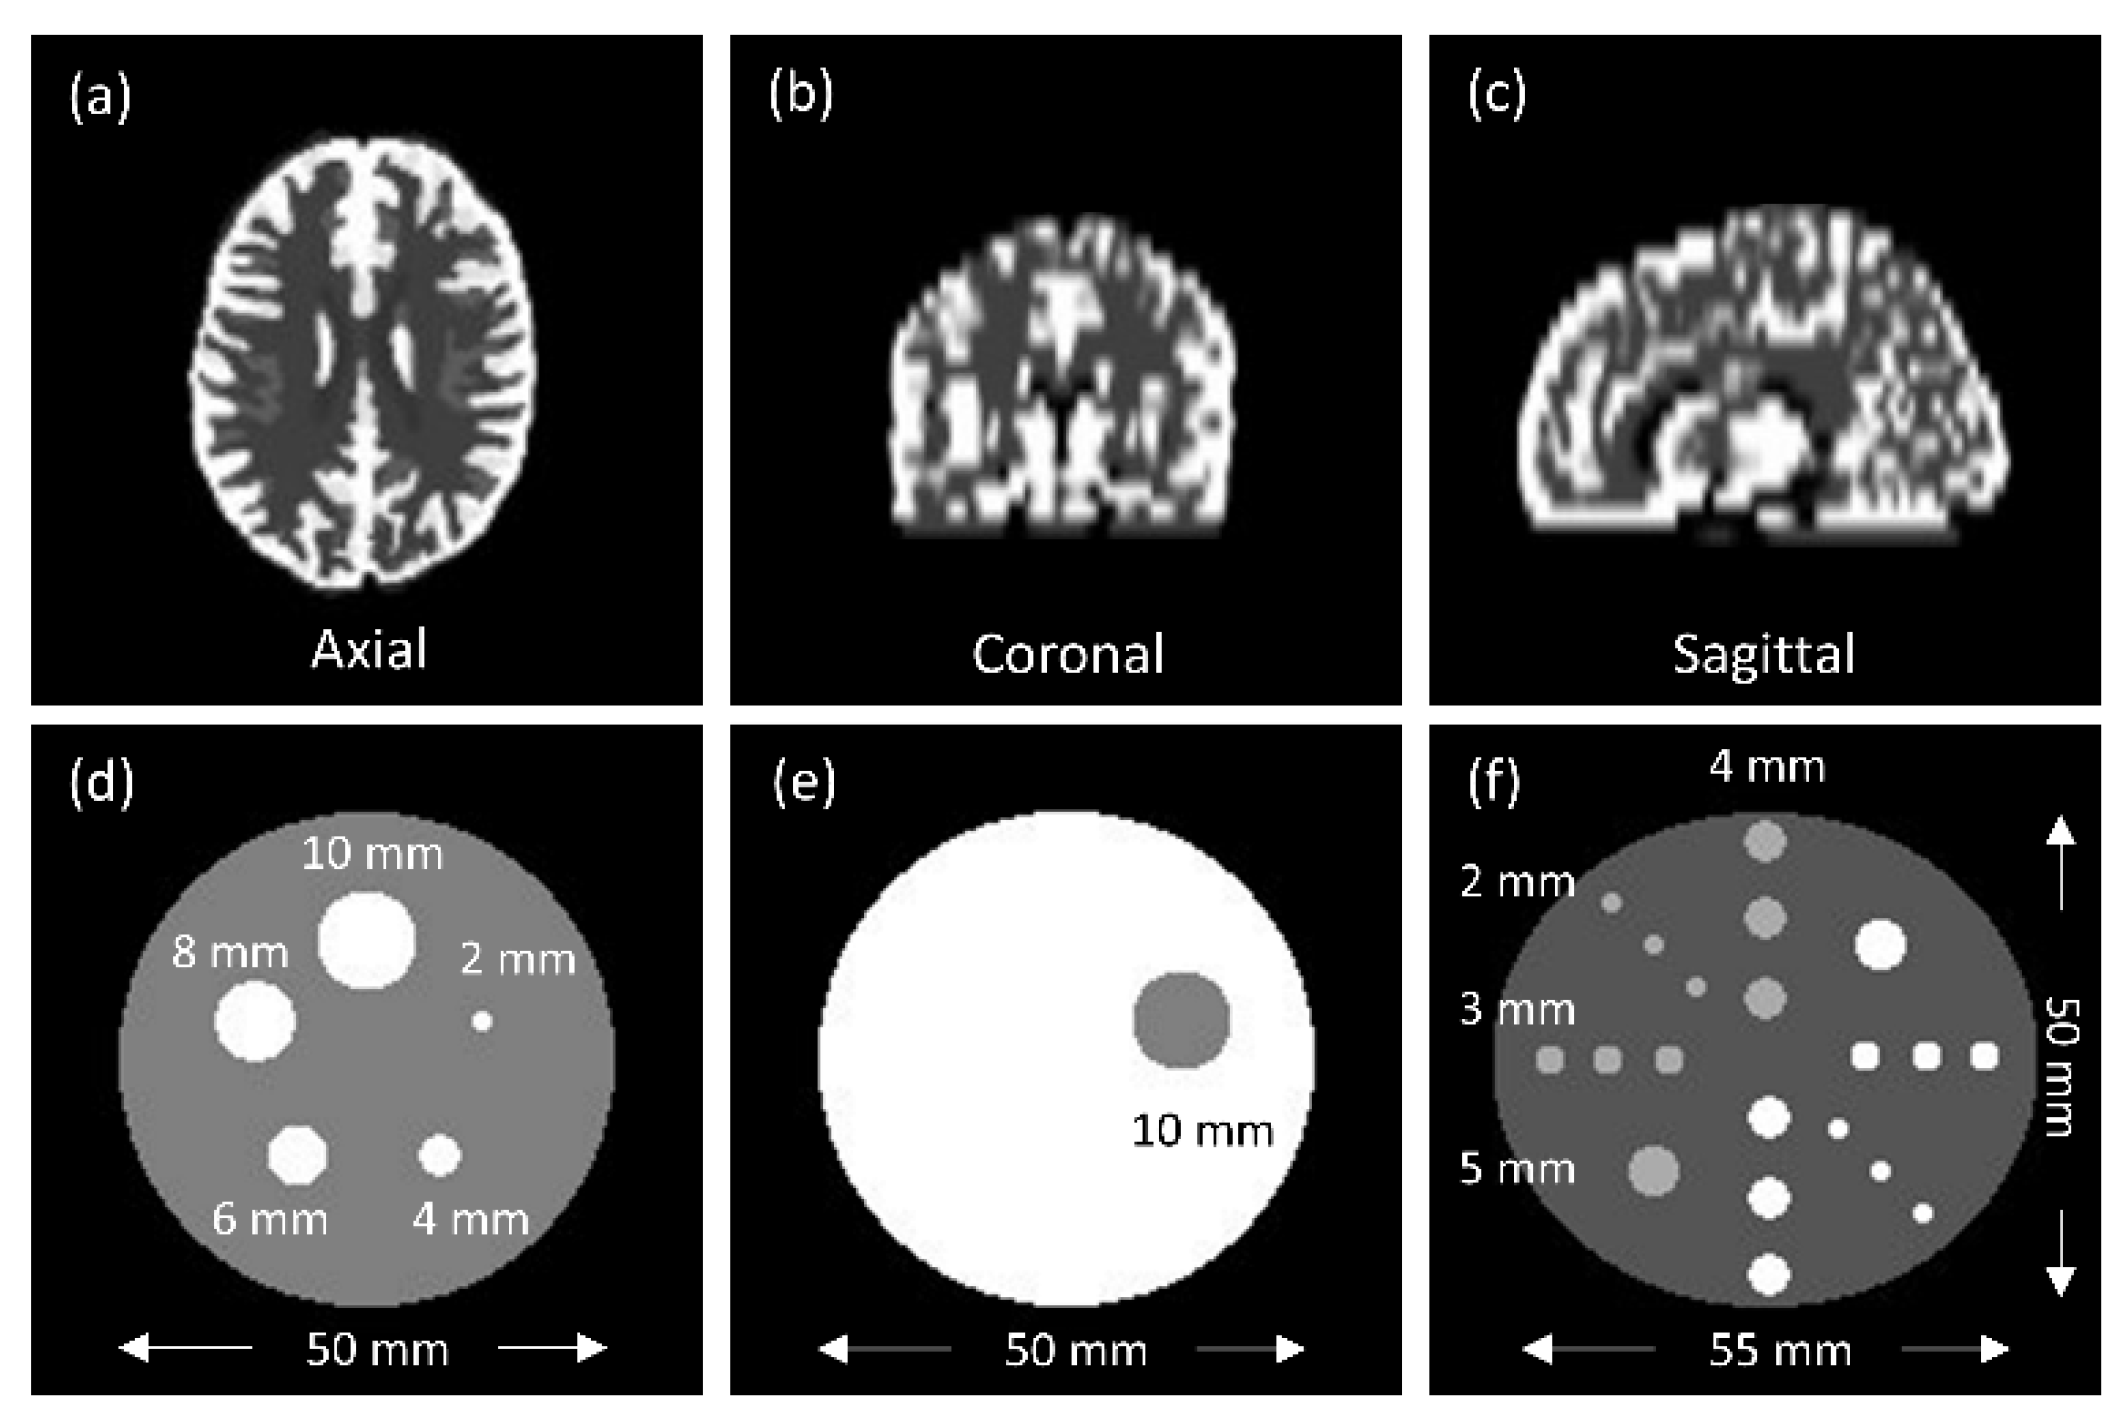

2.3. Phantom Design